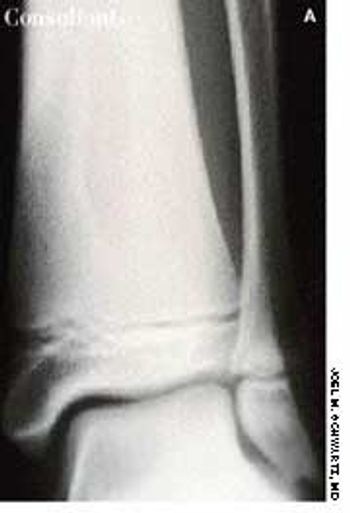

A 15-year-old boy had been experiencing pain in his distal left leg for 7 months. There was mild swelling, and an x-ray film of the lower leg revealed a sharply marginated, vertically oriented, tubular lucency in the metaphysis of the tibia (A). There was no cortical destruction, periosteal reaction, or pathologic fracture. An MRI at high field strength was performed to narrow the differential diagnosis.